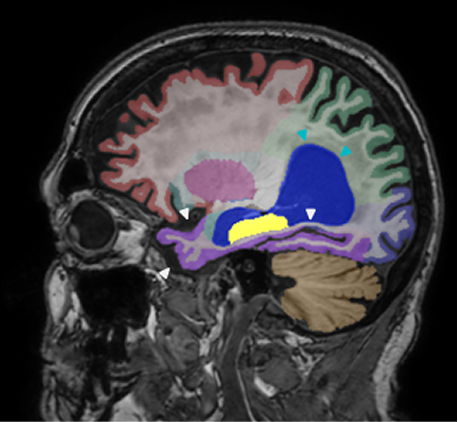

Retrospective brain volumetric analysis in a female patient diagnosed with Alzheimer’s disease at age 77 showed progressive brain atrophy over a 5-year period. The scans demonstrate both hippocampal volume loss and a clear left–right asymmetry.

PATIENT

Female patient diagnosed with Alzheimer's Disease at Age 77

Analysis period

5 years

regions of interest

Hippocampi

Inferior lateral ventricles

Age 72

Age 76

Age 77

Whole brain